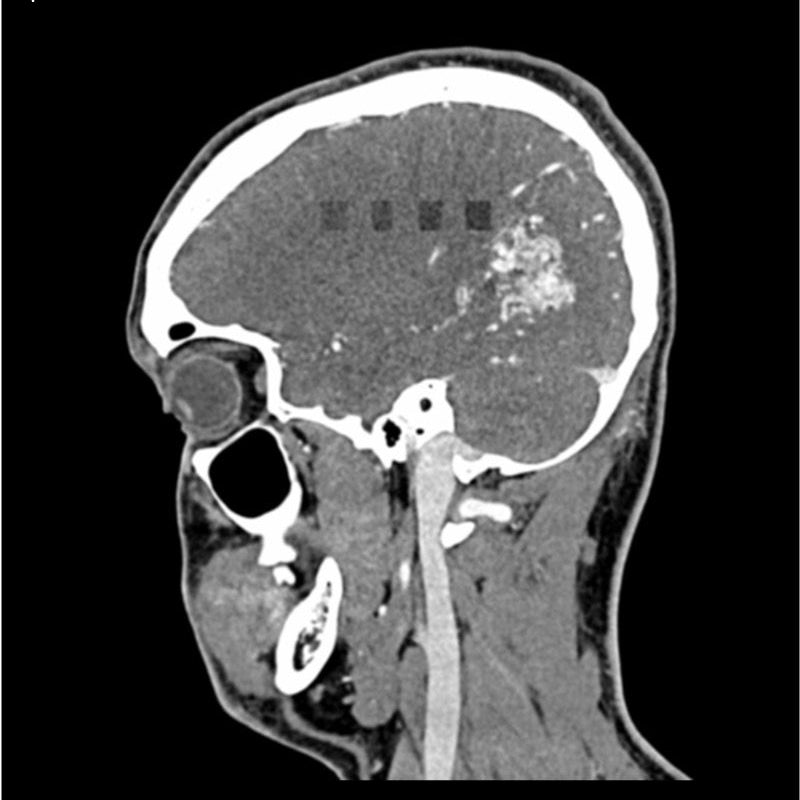

This phantom simulates a contrast medium enhanced head in arterial phase (CT angiography). It covers the vertex to the fifth cervical vertebra. The phantom has 10 low-contrast lesions in the centrum semiovale and the right hemisphere has an arteriovenous malformation.

The phantom can be used in CT (including CBCT) to evaluate and optimize imaging performance and AI-enabled diagnosis. It is also suited for training purposes. The phantom provides a detailed and realistic simulation of vascular structures, soft and bone tissue. Air voids are filled with a cellulose-polymer composite of approx. -160 HU.

Lesion diameter: 10 mm

Lesion height: 10.5 mm

Lesion contrast: Approx. -60 to -20 and 20 to 60 HU at 120 kVp